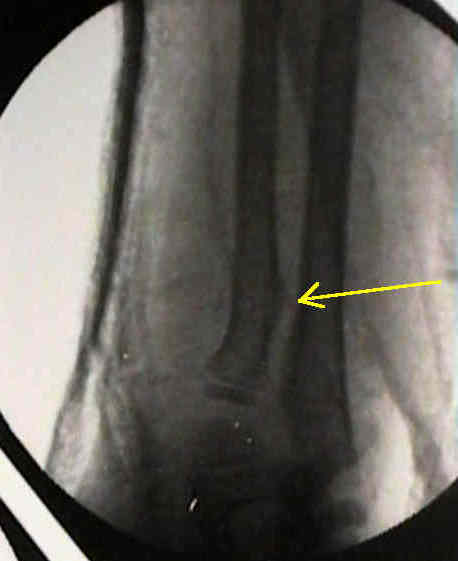

- angular / rotational deformity: (growth will not correct rotational deformity)

- distance from physis

- direction of angulation

- amount of deformity

between ages of 6-10 yrs

- less than 10 deg of angulation should remodel especially if frx is close to distal epiphysis;

- bayonet apposition may be acceptable, although end to end apposition is preferred;

- acceptable angulation is less than 15 deg, however, even more angulation may be preferable to resorting to open reduction;

- this is especially true if the reduction allows physiologic pronation and supination;